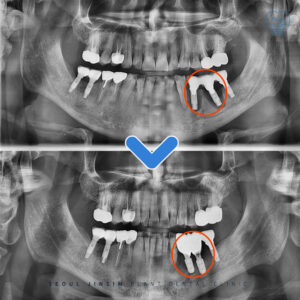

장안구치과 재신경치료 잘하는 치과 ,장안구치과 안녕하세요 수원 장안구에 위치하고 있는 장안구치과 서울진심플란트치과입니다. , 오늘은 오른쪽 아래 큰 어금니에 재신경치료를 진행하셨던 환자분의 사례를 소개해드리겠습니다. , 과거에 신경치료를 받았지만 이후 크라운 수복…